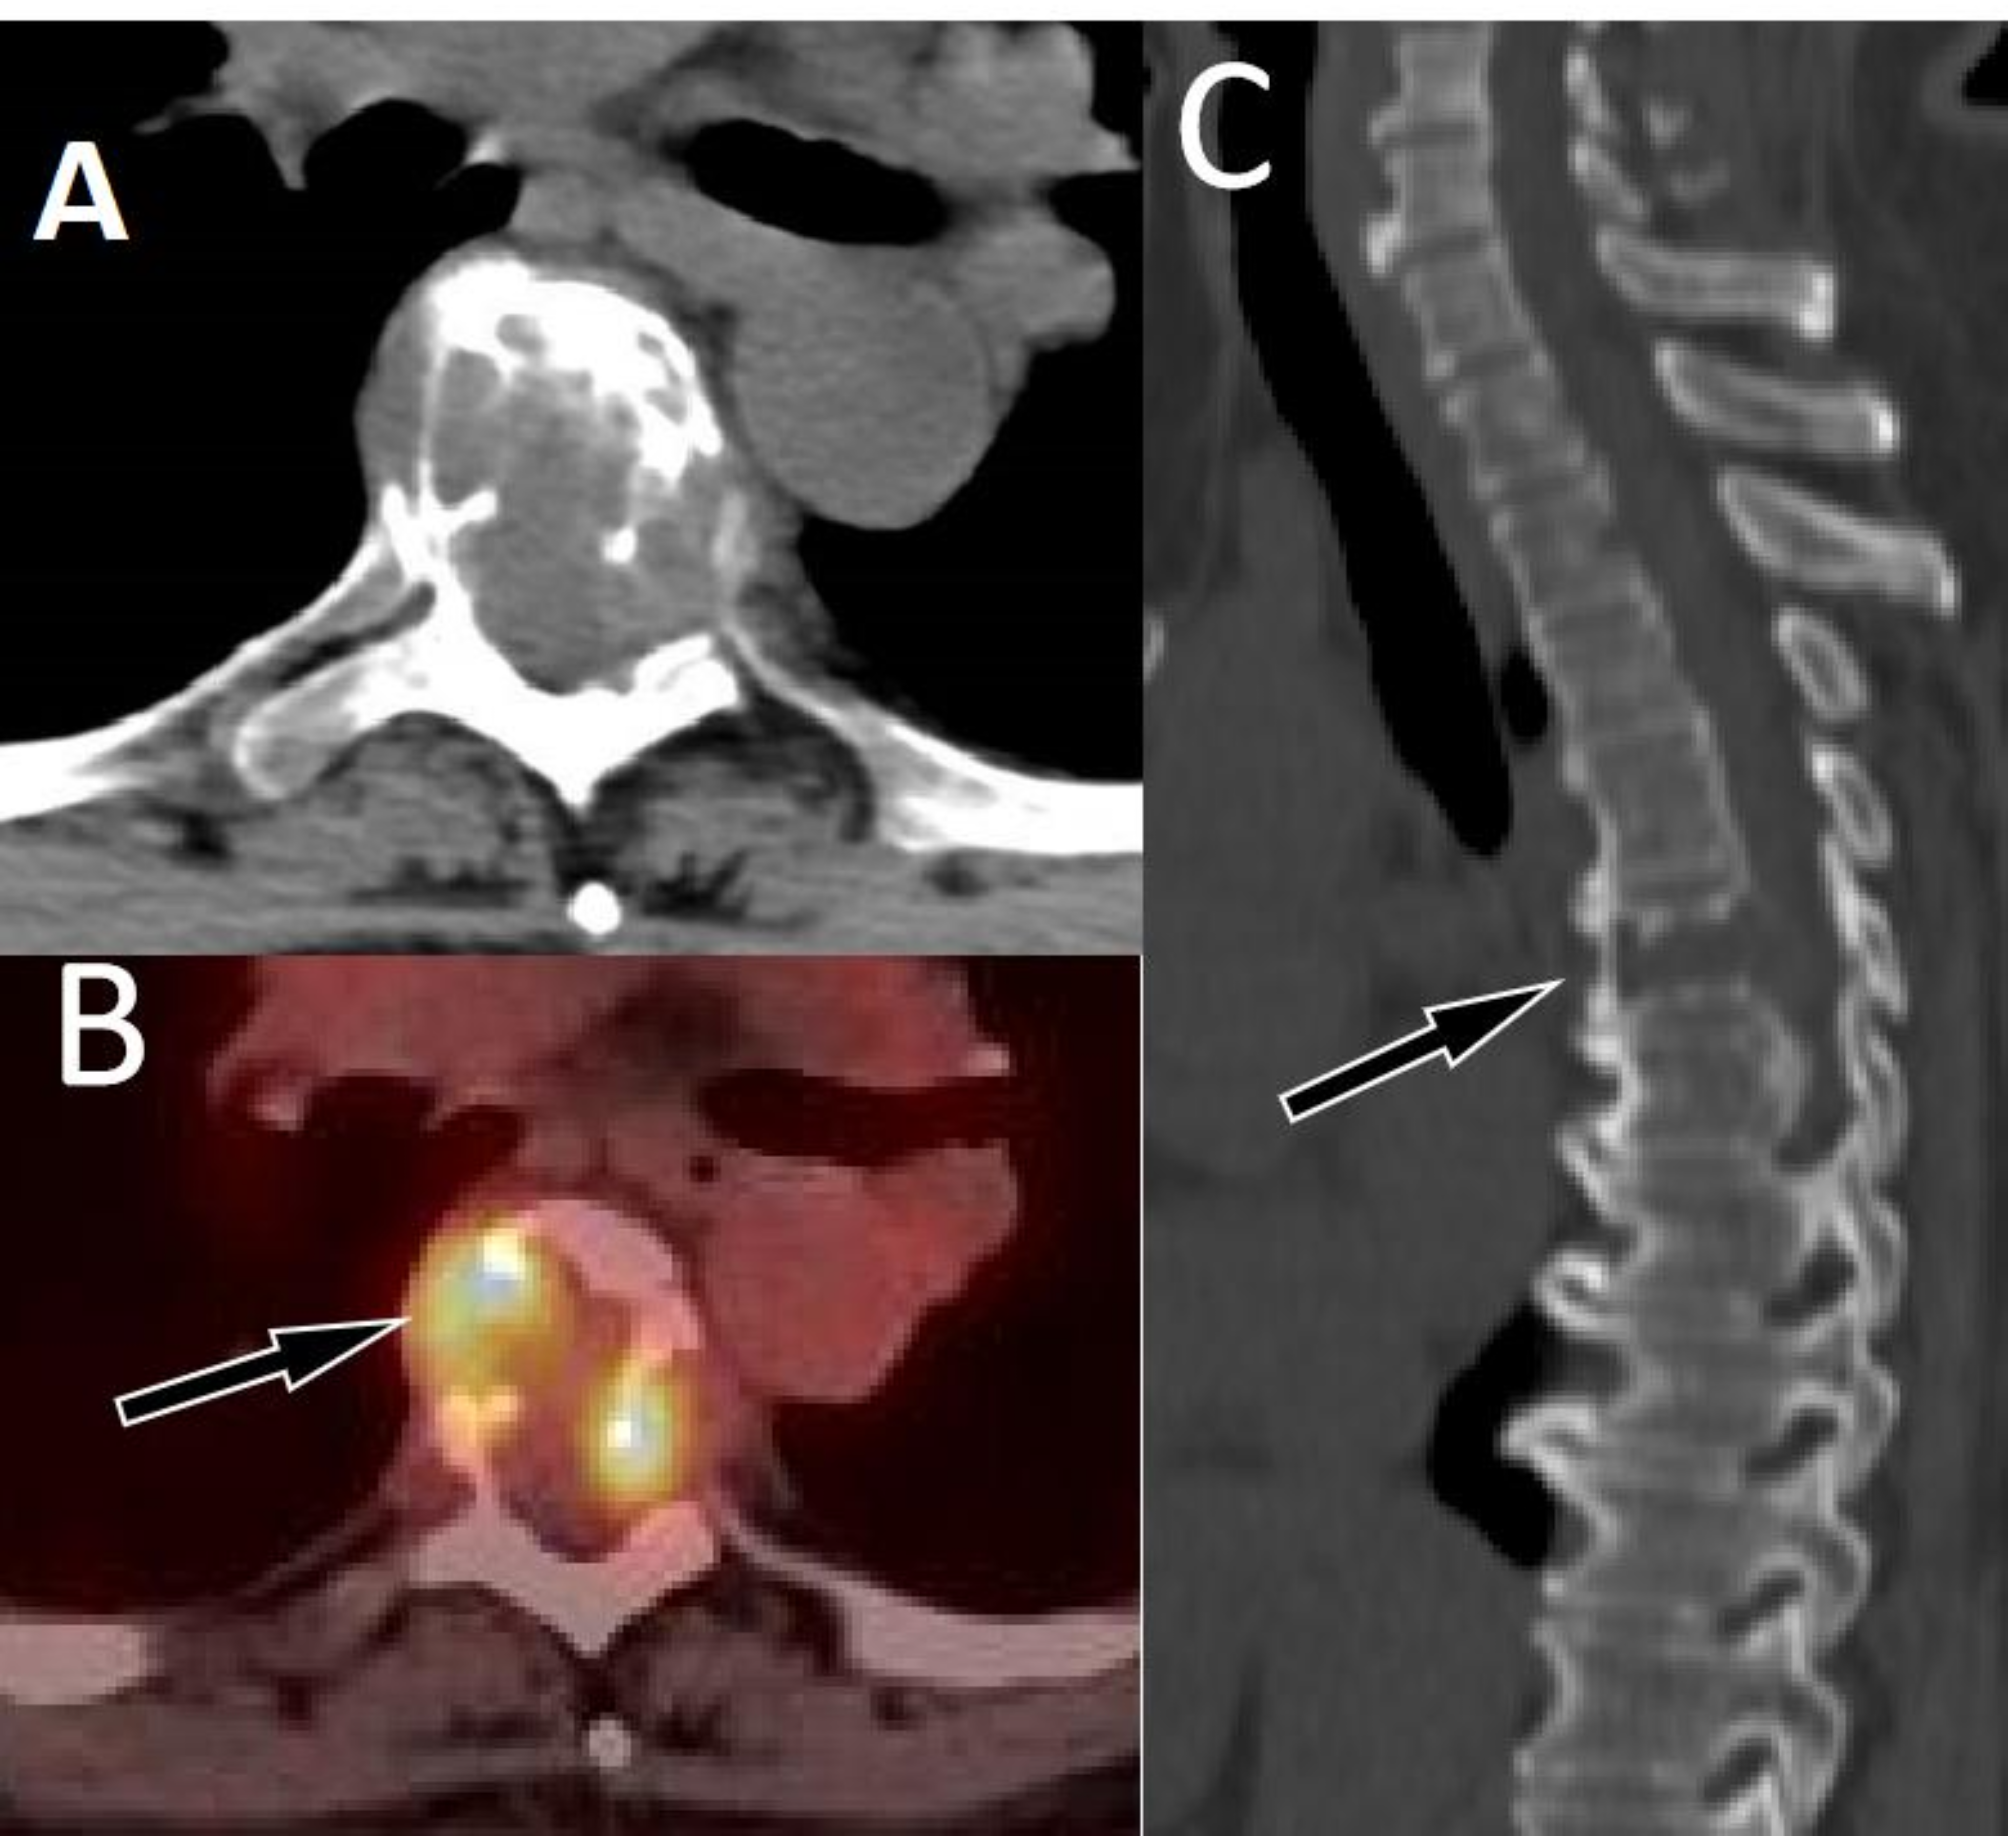

Fig. 5

A 51-year-old woman with EHE; (A) Axial CT revealed low-density osteolytic bone destruction shadow in the 6th thoracic vertebral body (arrow), which broke through the bone cortex and formed a soft tissue mass in the surrounding area; (B) The PET/CT fusion image of the corresponding area shows mildly increased 18F-FDG uptake (arrow), with a SUVmax of 6.0; (C) Sagittal CT reveals compressive changes in the vertebral body, with low-density cavity changes in the neutral state of the vertebral body (arrow), without sclerotic rims.